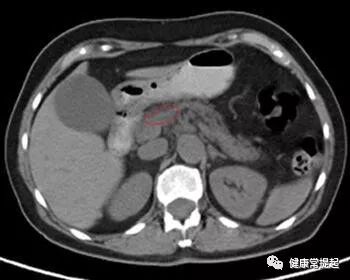

胰腺癌b超检查,胰腺癌的影像学检查